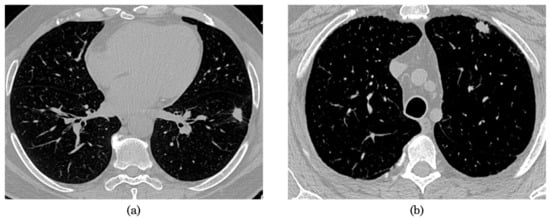

Figure 2.

Representation of lung axial slices with nodule from the NSCLC-Radiogenomics dataset of patients with (a) mutant EGFR and (b) wild-type EGFR.